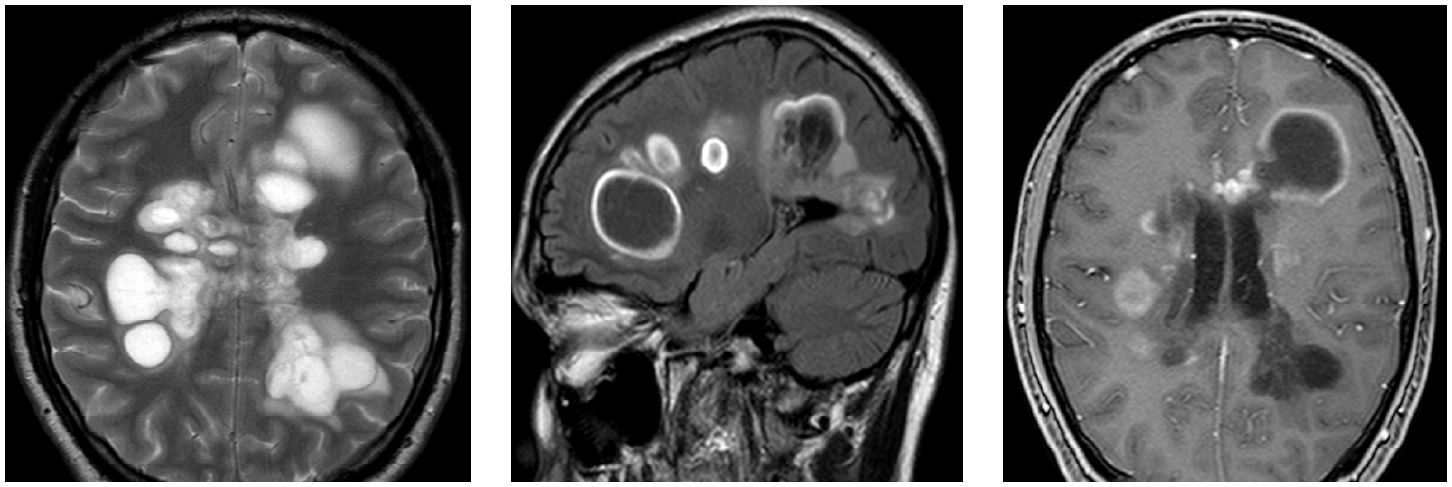

Сын пациента – Ш., 21 год – с августа 2019 г. при физических нагрузках, при ходьбе, в тепле – непостоянное снижение зрения сначала на левый, затем на правый глаз. Был осмотрен в Центре РС в январе 2020 г., диагноз: G37.9, вероятный рассеянный склероз, дебют. Состояние постепенно ухудшилось – наросли зрительные нарушения, появилась шаткость и чувствительные расстройства. Выполнено МРТ с контрастом 26.01.2020 (рис. 1): обострение, отек вокруг очагов, грубая активность процесса во все очагах, массивное накопление контраста, появление очагов в шейном отделе спинного мозга на уровне С2, также повышение сигнала и активность и области хиазмы справа, структурные изменения хиазмы слева.

Рис. 1. МРТ-изображения в режимах T2 ВИ и FLAIR, 26.01.2020

– 08.01.2020: головной мозг – очаги демиелинизации в белом веществе, в мозолистом теле, мозжечке, с признаками отека. Джо 10–15 очагов. Лейкоареоз;

– 26.01.2020: головной мозг – отрицательная динамика в сравнении с 08.01.2020, обострение по МРТ, отек вокруг очагов, грубая активность процесса во всех очагах, массивное накопление контраста, появление очагов в шейном отделе спинного мозга на уровне С2, также повышение сигнала и активность и области хиазмы справа, структурные изменения хиазмы слева;